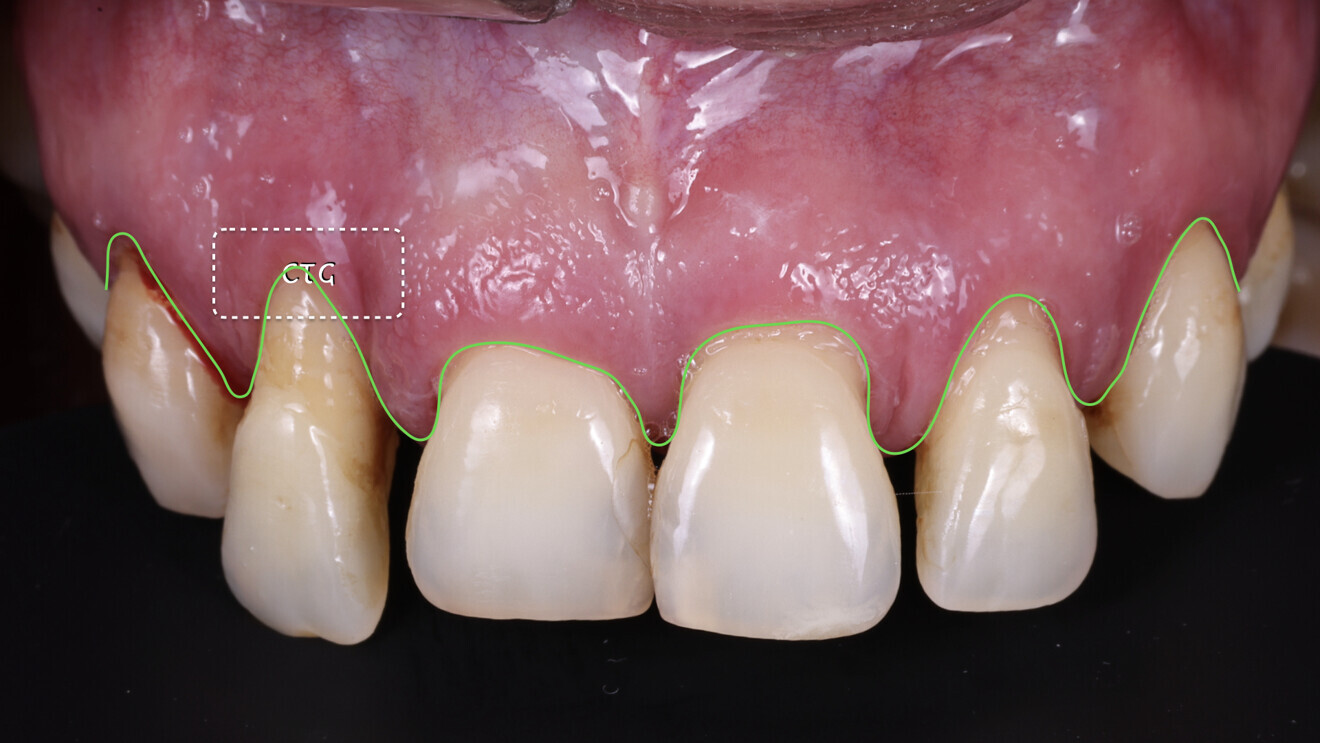

Fig. 4: Soft-tissue profile. We observed an excess of tissue overall except in the area of tooth #12, where a connective tissue graft (CTG) would be needed.

From an occlusal perspective, the patient exhibited both an excessive overjet and overbite (Fig. 3). However, her gingival architecture remained largely intact. Despite the presence of deep, untreatable periodontal pockets, there was minimal recession, thanks to her thick periodontal biotype (Fig. 4). This offered us an advantage. With careful planning and proper design, we were confident that we could preserve and slightly modify her gingival tissue to meet her aesthetic goals.

The following day, a connective tissue graft was placed in the area of tooth #12 to enhance the soft-tissue profile, and the temporary restoration was delivered. After the delivery, the patient was allowed to heal for a period of four months, allowing for proper implant integration and soft-tissue healing (Figs. 19–22).